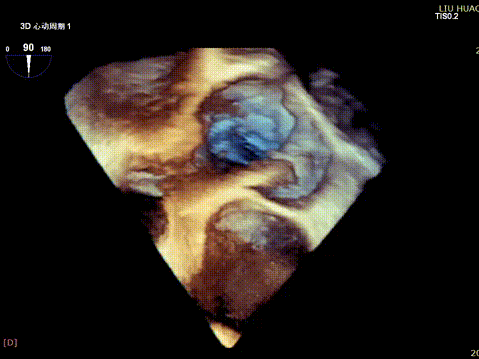

Tricuspid Valve Annuloplasty Stage:Subsequently, via the right internal jugular vein approach, the K-clip® transcatheter tricuspid valve annuloplasty system was delivered to the right atrium. With the assistance of three-dimensional ultrasound stereoscopic views, a 12T clip was successfully implanted at the posteroseptal commissural annulus of the tricuspid valve, and a 14T clip at the anteroposterior commissural annulus, achieving effective constriction of the dilated annulus. Immediate postoperative assessment demonstrated that tricuspid regurgitation was improved from severe (4+) to mild (1+) instantaneously.

5.Perform the same procedure for the second clip; the clip morphology is stable under 3D imaging

Annuloplasty Effect: The tricuspid valve annulus area was reduced from 9.96 cm² to 4.6 cm², representing a 53% decrease in annulus area.

Preoperative regurgitation (severe)

Postoperative regurgitation (trivial)

Surgical Outcome: Severe tricuspid regurgitation (4+) was reduced to mild tricuspid regurgitation (1+).